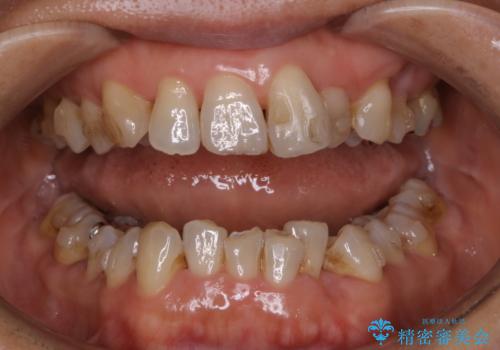

インビザラインの治療中の患者様のクリーニング前後写真です。

- インビザラインの矯正治療中に歯石や着色(ステイン)が付着してしまっていたため、歯科衛生士による専門的クリーニングを行いました。

今回はお口全体に歯石や着色(ステイン)が付着していたため、自費のPMTC(クリーニング)60分コースをご案内し、徹底的に除去しました。